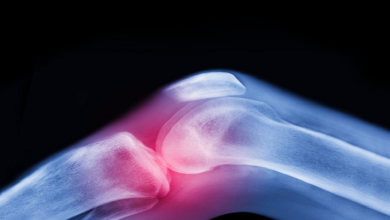

دراسة جديدة: الميتفورمين قد يساعد في تخفيف آلام الركبة لمصابي السمنة وهشاشة العظام

أجرى فريق من الباحثين في جامعة موناش دراسة جديدة استهدفت تأثير أحد الأدوية الشائعة في علاج مرض السكري على الأشخاص الذين يعانون من التهاب مفاصل الركبة وزيادة الوزن أو السمنة. وأظهرت الدراسة أن الميتفورمين، المستخدم عادة لعلاج السكري…

دواء شائع للسكري يخفف آلام التهاب مفاصل الركبة

النقابي الجنوبي/متابعة خاصة أجرى فريق من الباحثين في جامعة موناش دراسة جديدة استهدفت تأثير أحد الأدوية الشائعة في علاج مرض السكري على الأشخاص الذين يعانون من التهاب مفاصل الركبة وزيادة الوزن أو السمنة. وأظهرت الدراسة أن الميتفورمين، المستخدم عادة لعلاج…